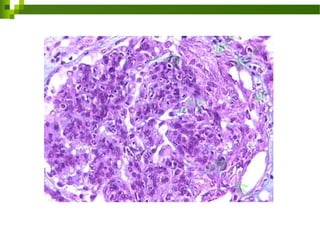

Patología

Histológicamente se caracteriza

 Lesiones situadas en el espacio de

 Células epiteliales parietales y

 Células proliferadas que pueden

histológicos o presentarse junto con